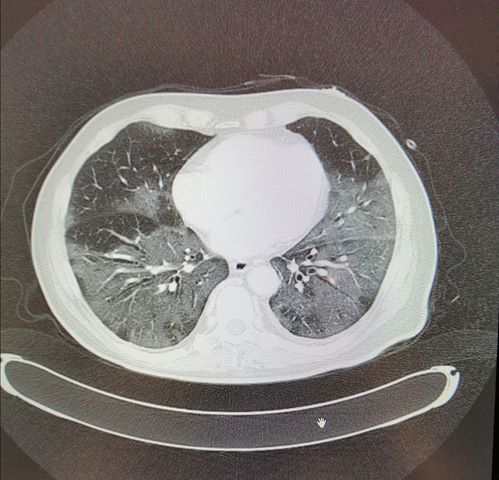

Most eljött az ideje, hogy kellenek azok az ágyak. Az üres termek gyorsan telnek. A kijelzőkön ott vannak a nevek, a táblák színe általában attól függ, hogy melyik műtőbe tartozik a páciens, most ezek mind pirosan világítanak, de műtét helyett a diagnózissal: kétoldali szövetközti tüdőgyulladás.”

„Mondjátok meg, melyik influenza okoz ilyen gyors romlást?” – írja a doktor, majd orvosi magyarázatba kezd arról, hogy a normál influenzában a vírus lerontja a védelmi mechanizmusokat, aztán baktérium okoz gyulladást. A Covid-19 viszont egyből a tüdőt fertőzi, és teszi nehézzé, hogy ellássa a feladatát.

Kiadták a parancsot: plusz segítség kell a sürgősségi osztályra. Az emberek egy gyors mítingen megtanulják a szoftver kezelését, aztán pár perc múlva már ott is vannak, a fronton. A PC képernyőjén mindig ugyanaz: láz és nehéz légzés, láz és köhögés, légzési problémák stb. A vizsgálatoknak, a röntgennek mindig ugyanaz az eredménye:

kétoldali szövetközi tüdőgyulladás, kétoldali szövetközi tüdőgyulladás, kétoldali szövetközi tüdőgyulladás.